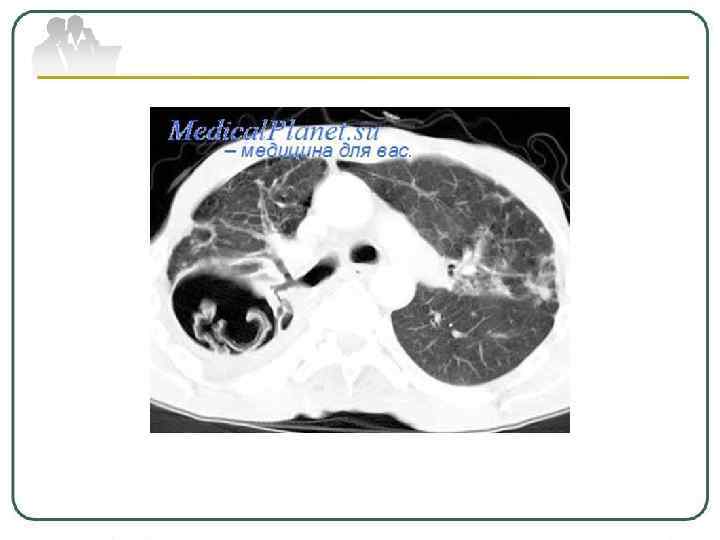

Кавернозный туберкулез легких характеризуется наличием сформированной каверны с отсутствием выраженных фиброзных изменений в окружающей каверну легочной ткани. Развивается кавернозный туберкулез у больных инфильтративным, диссеминированным, очаговым туберкулезом, при распаде туберкулем; при позднем выявлении заболевания, когда фаза распада завершается формированием каверн, а признаки исходной формы исчезают.

Фиброзно-кавернозный туберкулез легких характеризуется наличием фиброзной каверны, развитием фиброзных изменений в окружающей каверну легочной ткани. Для него характерны очаги бронхогенного отсева различной давности. Как правило, поражается дренирующий каверну бронх. Развиваются и другие морфологические изменения в легких: пневмосклероз, эмфизема, бронхоэктазы. Формируется фиброзно-кавернозный туберкулез из инфильтративного, кавернозного или диссеминированного процесса при прогрессирующем течении заболевания. Протяженность изменений в легких может быть различной; процесс бывает односторонним и двусторонним с наличием одной или множества каверн.